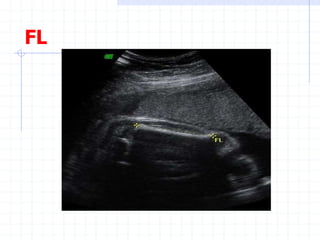

Assessment of fetal growth by

Biometry:

FL